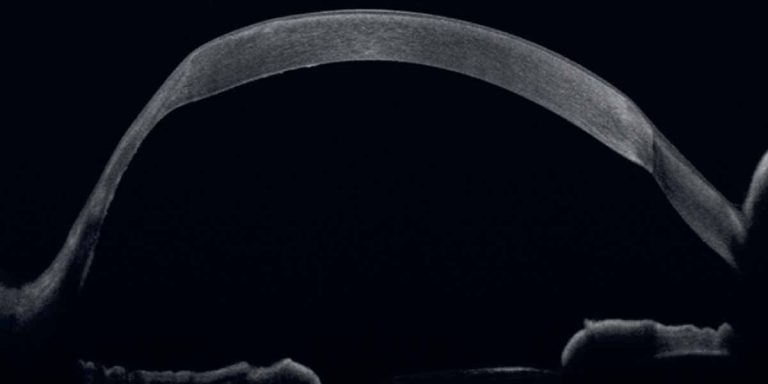

Will Keratoplasty for Keratoconus Still Be Needed in 2040?

At the 10th SAoO Congress in Lucerne, Dr. Emilio Torres-Netto examined how advances in keratoconus care may further reduce the need for keratoplasty by 2040